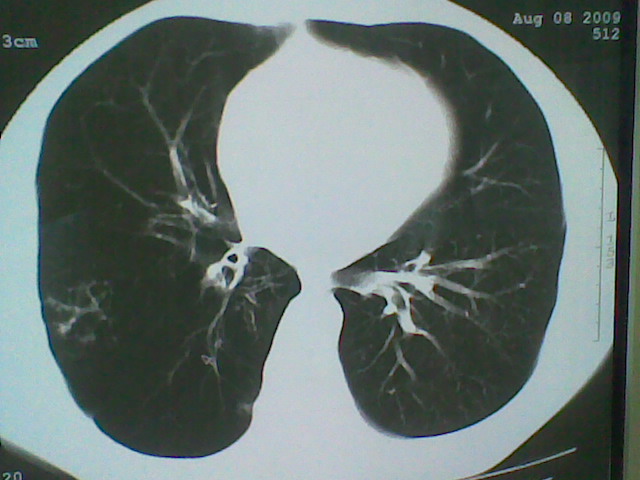

标题: CT21512:支扩伴感染?

患者女。咳嗽数天,咯血半天。

我们报的是支扩伴感染?

支持 支气管扩张并感染。

支持楼主意见,考虑支气管扩张并感染。

支气管扩张并感染。